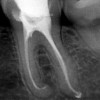

Quando una carie o un trauma colpiscono il nervo, l’endodonzia (comunemente nota come devitalizzazione) è l'unica soluzione per salvare l'elemento dentale ed evitare l'estrazione. Si tratta di una delle branche più delicate dell'odontoiatria: la terapia consiste nel disinfettare, sagomare e sigillare in modo tridimensionale l'intero sistema dei canali radicolari.

Tecnologia di precisione: affrontiamo la complessità anatomica dei canali con protocolli rigorosi per garantire il successo della cura a lungo termine.